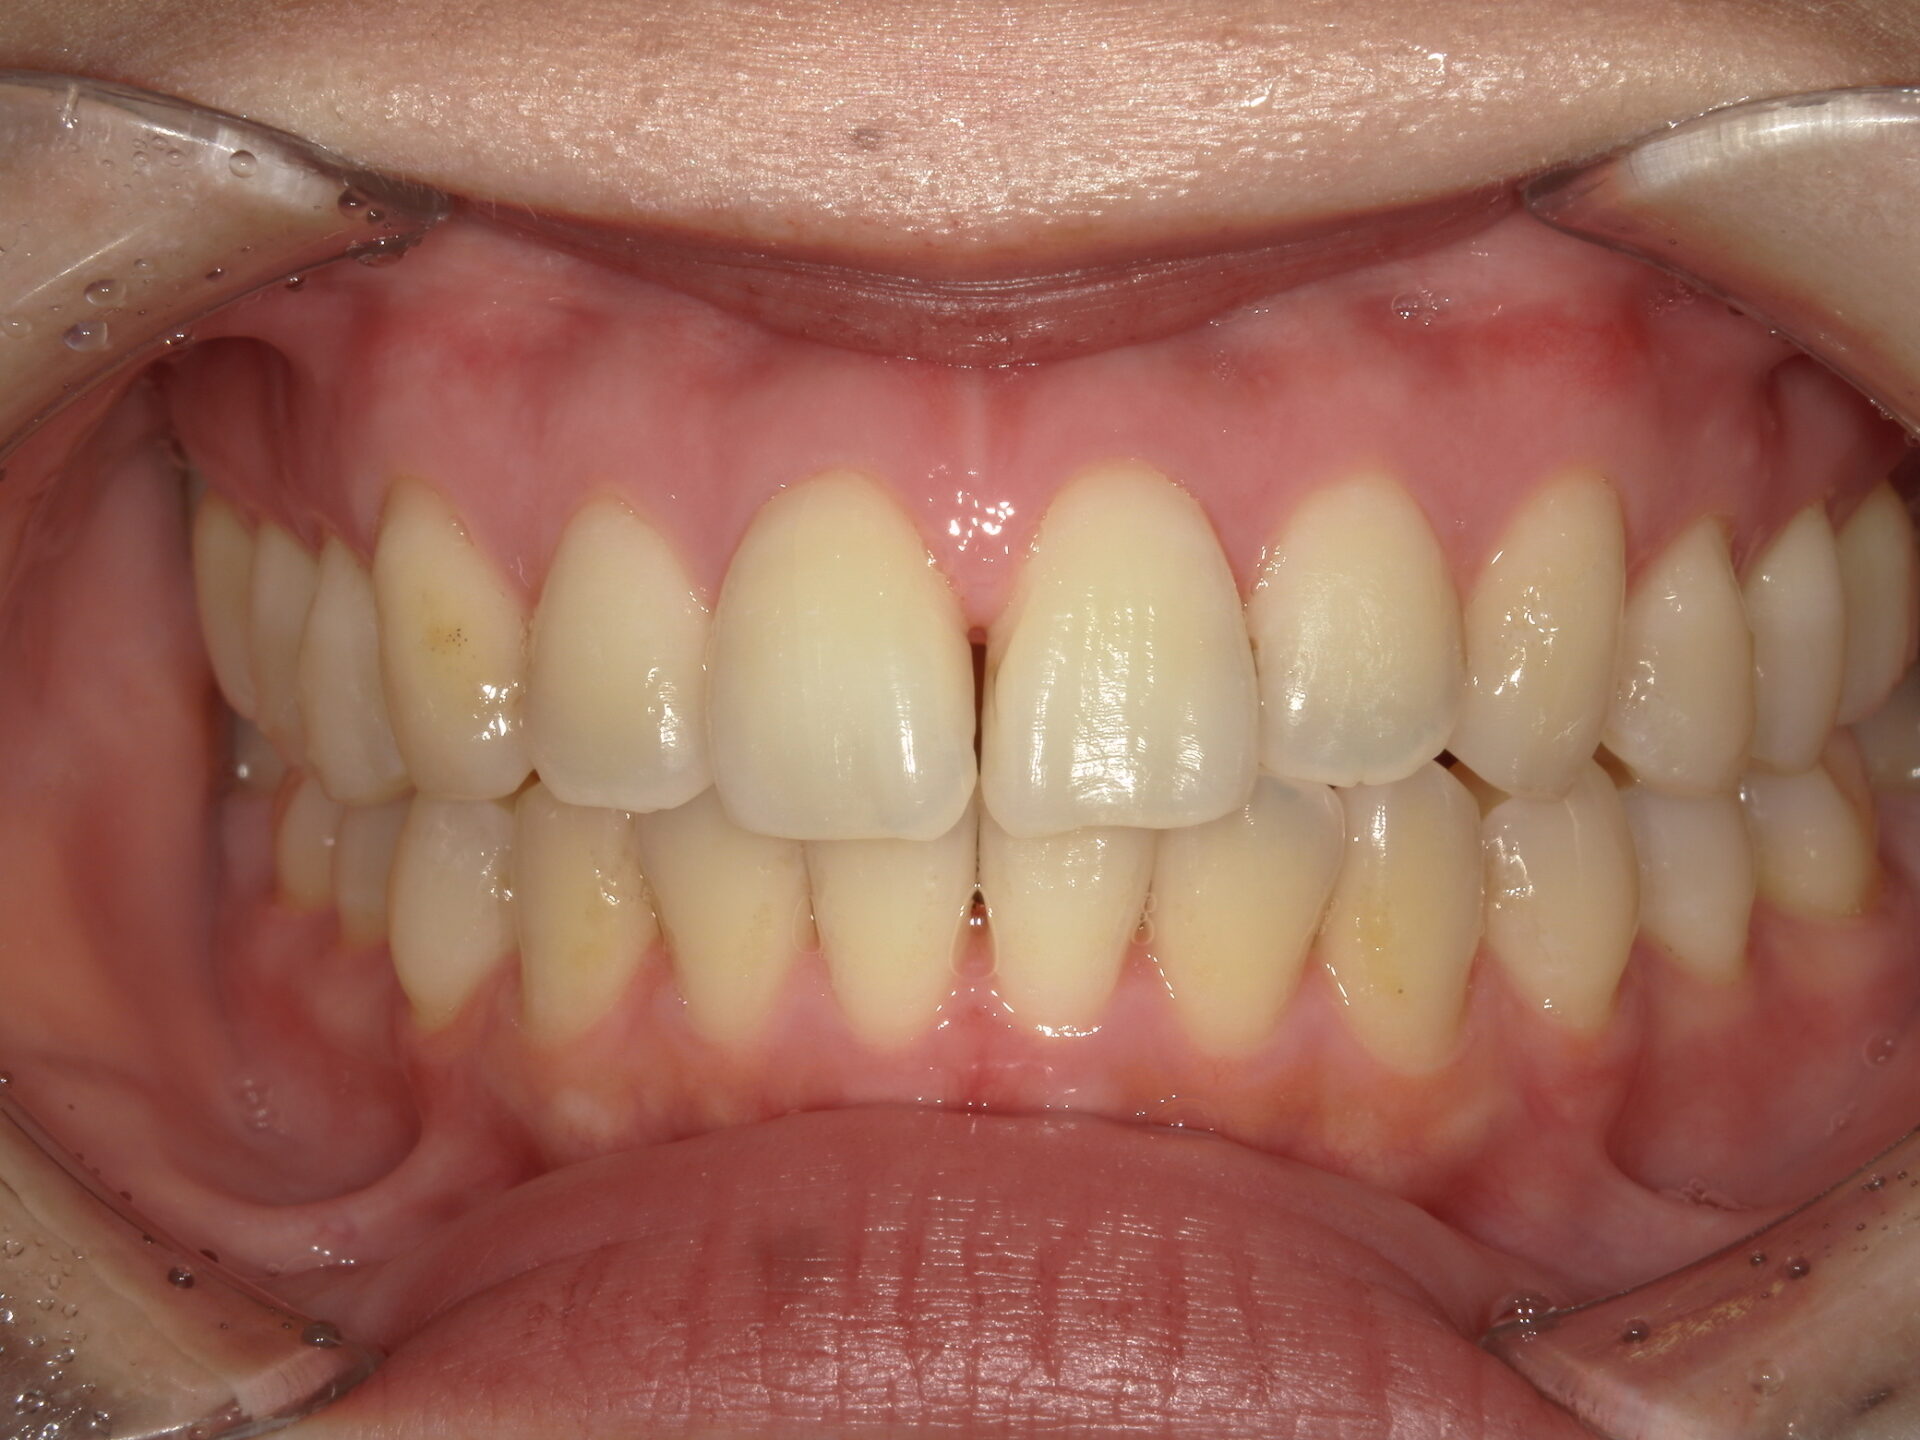

before

患者さんの年齢 20代 女性 症状 ガタガタを治したい 治療内容 マウスピース矯正治療 費用 90万(税抜) 治療期間・回数 治療期間2年、通院回数10回 メリット 笑顔が綺麗 デメリット・リスク 期間がかかることがある - マウスピース矯正